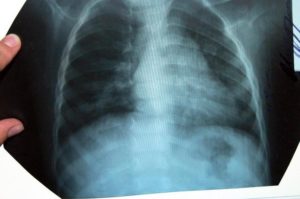

Клинически повторное заболевание, как правило, проявляется значительно сильнее, чем первичный случай. Однако на начальных этапах его трудно распознать, поскольку пациент может считать, что вновь появившиеся симптомы являются следствием ранее перенесенной болезни. Рентгенологическое обследование легких играет ключевую роль в определении характера протекания заболевания.

- Рентгенологическое исследование демонстрирует увеличение пораженной области или изменение характера заболевания на очаговое, что подразумевает наличие множественных поражений.

Установить более точный диагноз с определением степени поражения легкого (также, как распознать бронхит у ребенка и любое другое бронхолегочное заболевание) можно с помощью рентгенографии.

В медицинских источниках можно встретить различные определения повторной пневмонии. В педиатрической практике это заболевание характеризуется как два или более случая в течение одного календарного года, либо более трех эпизодов за неограниченный период времени. При этом рецидив подтверждается рентгенографическими данными, которые показывают освобождение легочной ткани при наличии инфильтрации.